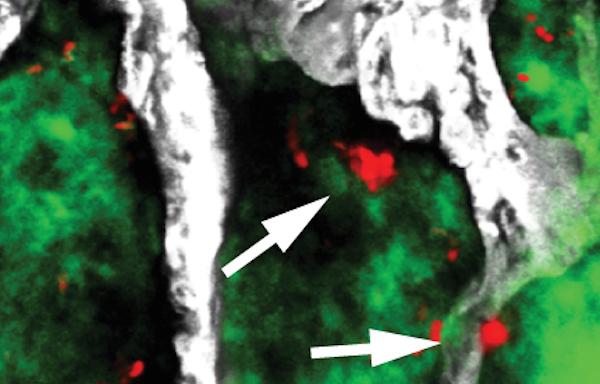

Using a groundbreaking technique called intravital two-photon microscopy, the researchers tracked the fate of sleeping cancer cells in the tibia (the main bone in the long part of the leg) of a living mouse. They introduced cells from multiple myeloma (a cancer of blood cells that arises in bone) into the mouse, and watched as a small number of the cells lodged in the tibia and 'went to sleep'. These vanishingly rare sleeping cells could be detected because they contained a fluorescent dye that was lost rapidly from dividing (wakeful) cells.

"We were able to show that myeloma cells are usually kept asleep by close association with a layer of osteoblast-like cells, called bone-lining cells, in the endosteum (an internal surface within bone). The bone-lining cells are essentially inactive, so we can think of them as providing a quiet environment in which myeloma cells sleep undisturbed.

"Crucially, we can wake those myeloma cells by activating osteoclasts, which break down bone tissue. We think the osteoclasts are physically changing the local environment of the cancer cells and waking them up in the process - as if they were literally throwing them out of bed.